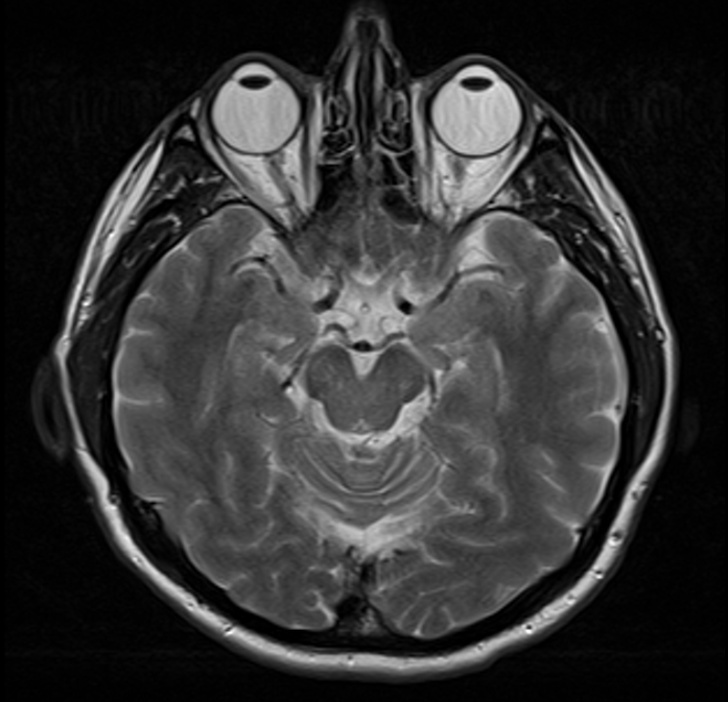

2. МРТ-знімок здорового головного мозку людини